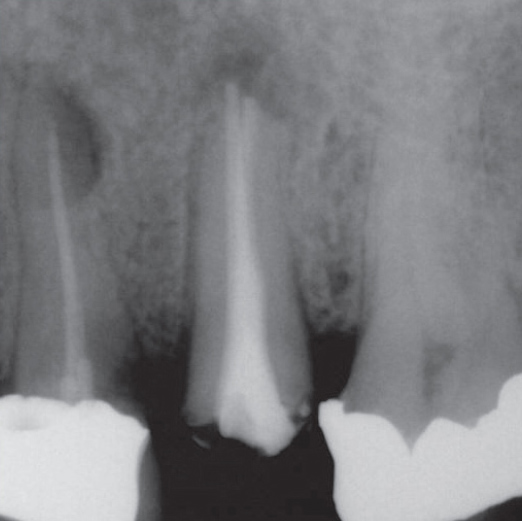

Before

Before Root Canal treatment